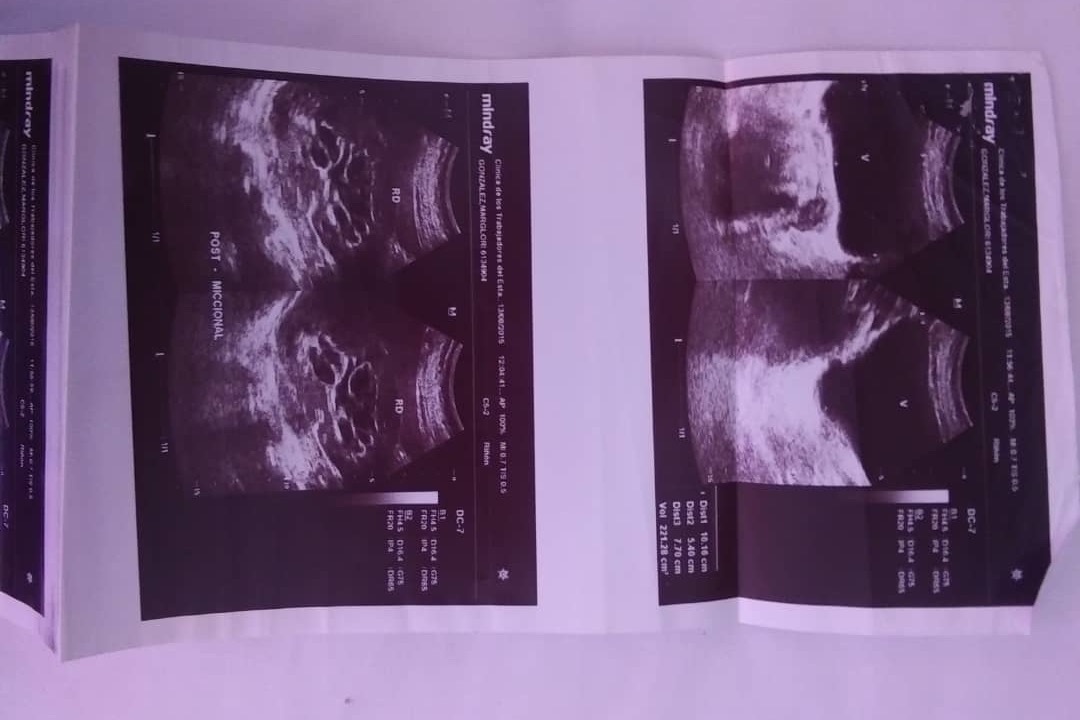

Soy un paciente con riñon único derecho.

Y me diagnosticaron quistes parapielicos derechos y pielocaliectasia derecha.

Debo ser sometida a una intervención para colocación de Catéter Doble J.